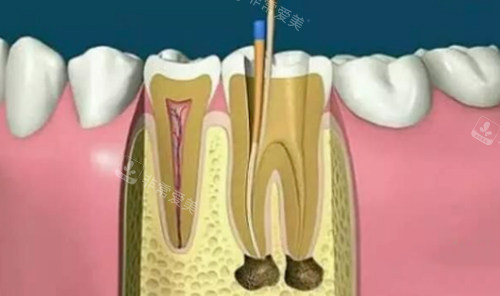

牙科根管治疗示意图

根管治疗动画演示